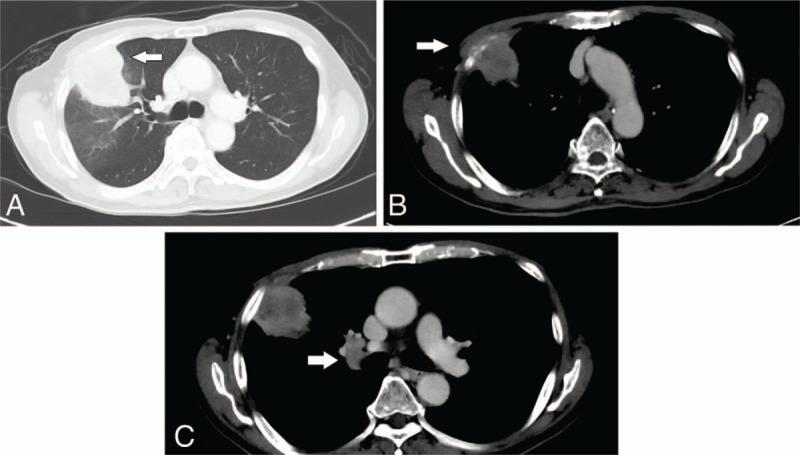

He has survived more than two years since his initial diagnosis, maintaining his good performance status. Serial imaging with computed tomography scans showed tumour regression and near-complete resolution of his disease.

自初次诊断以来,他已存活两年多,保持了良好的身体状况。计算机断层扫描的系列成像显示肿瘤消退且疾病几乎完全缓解。